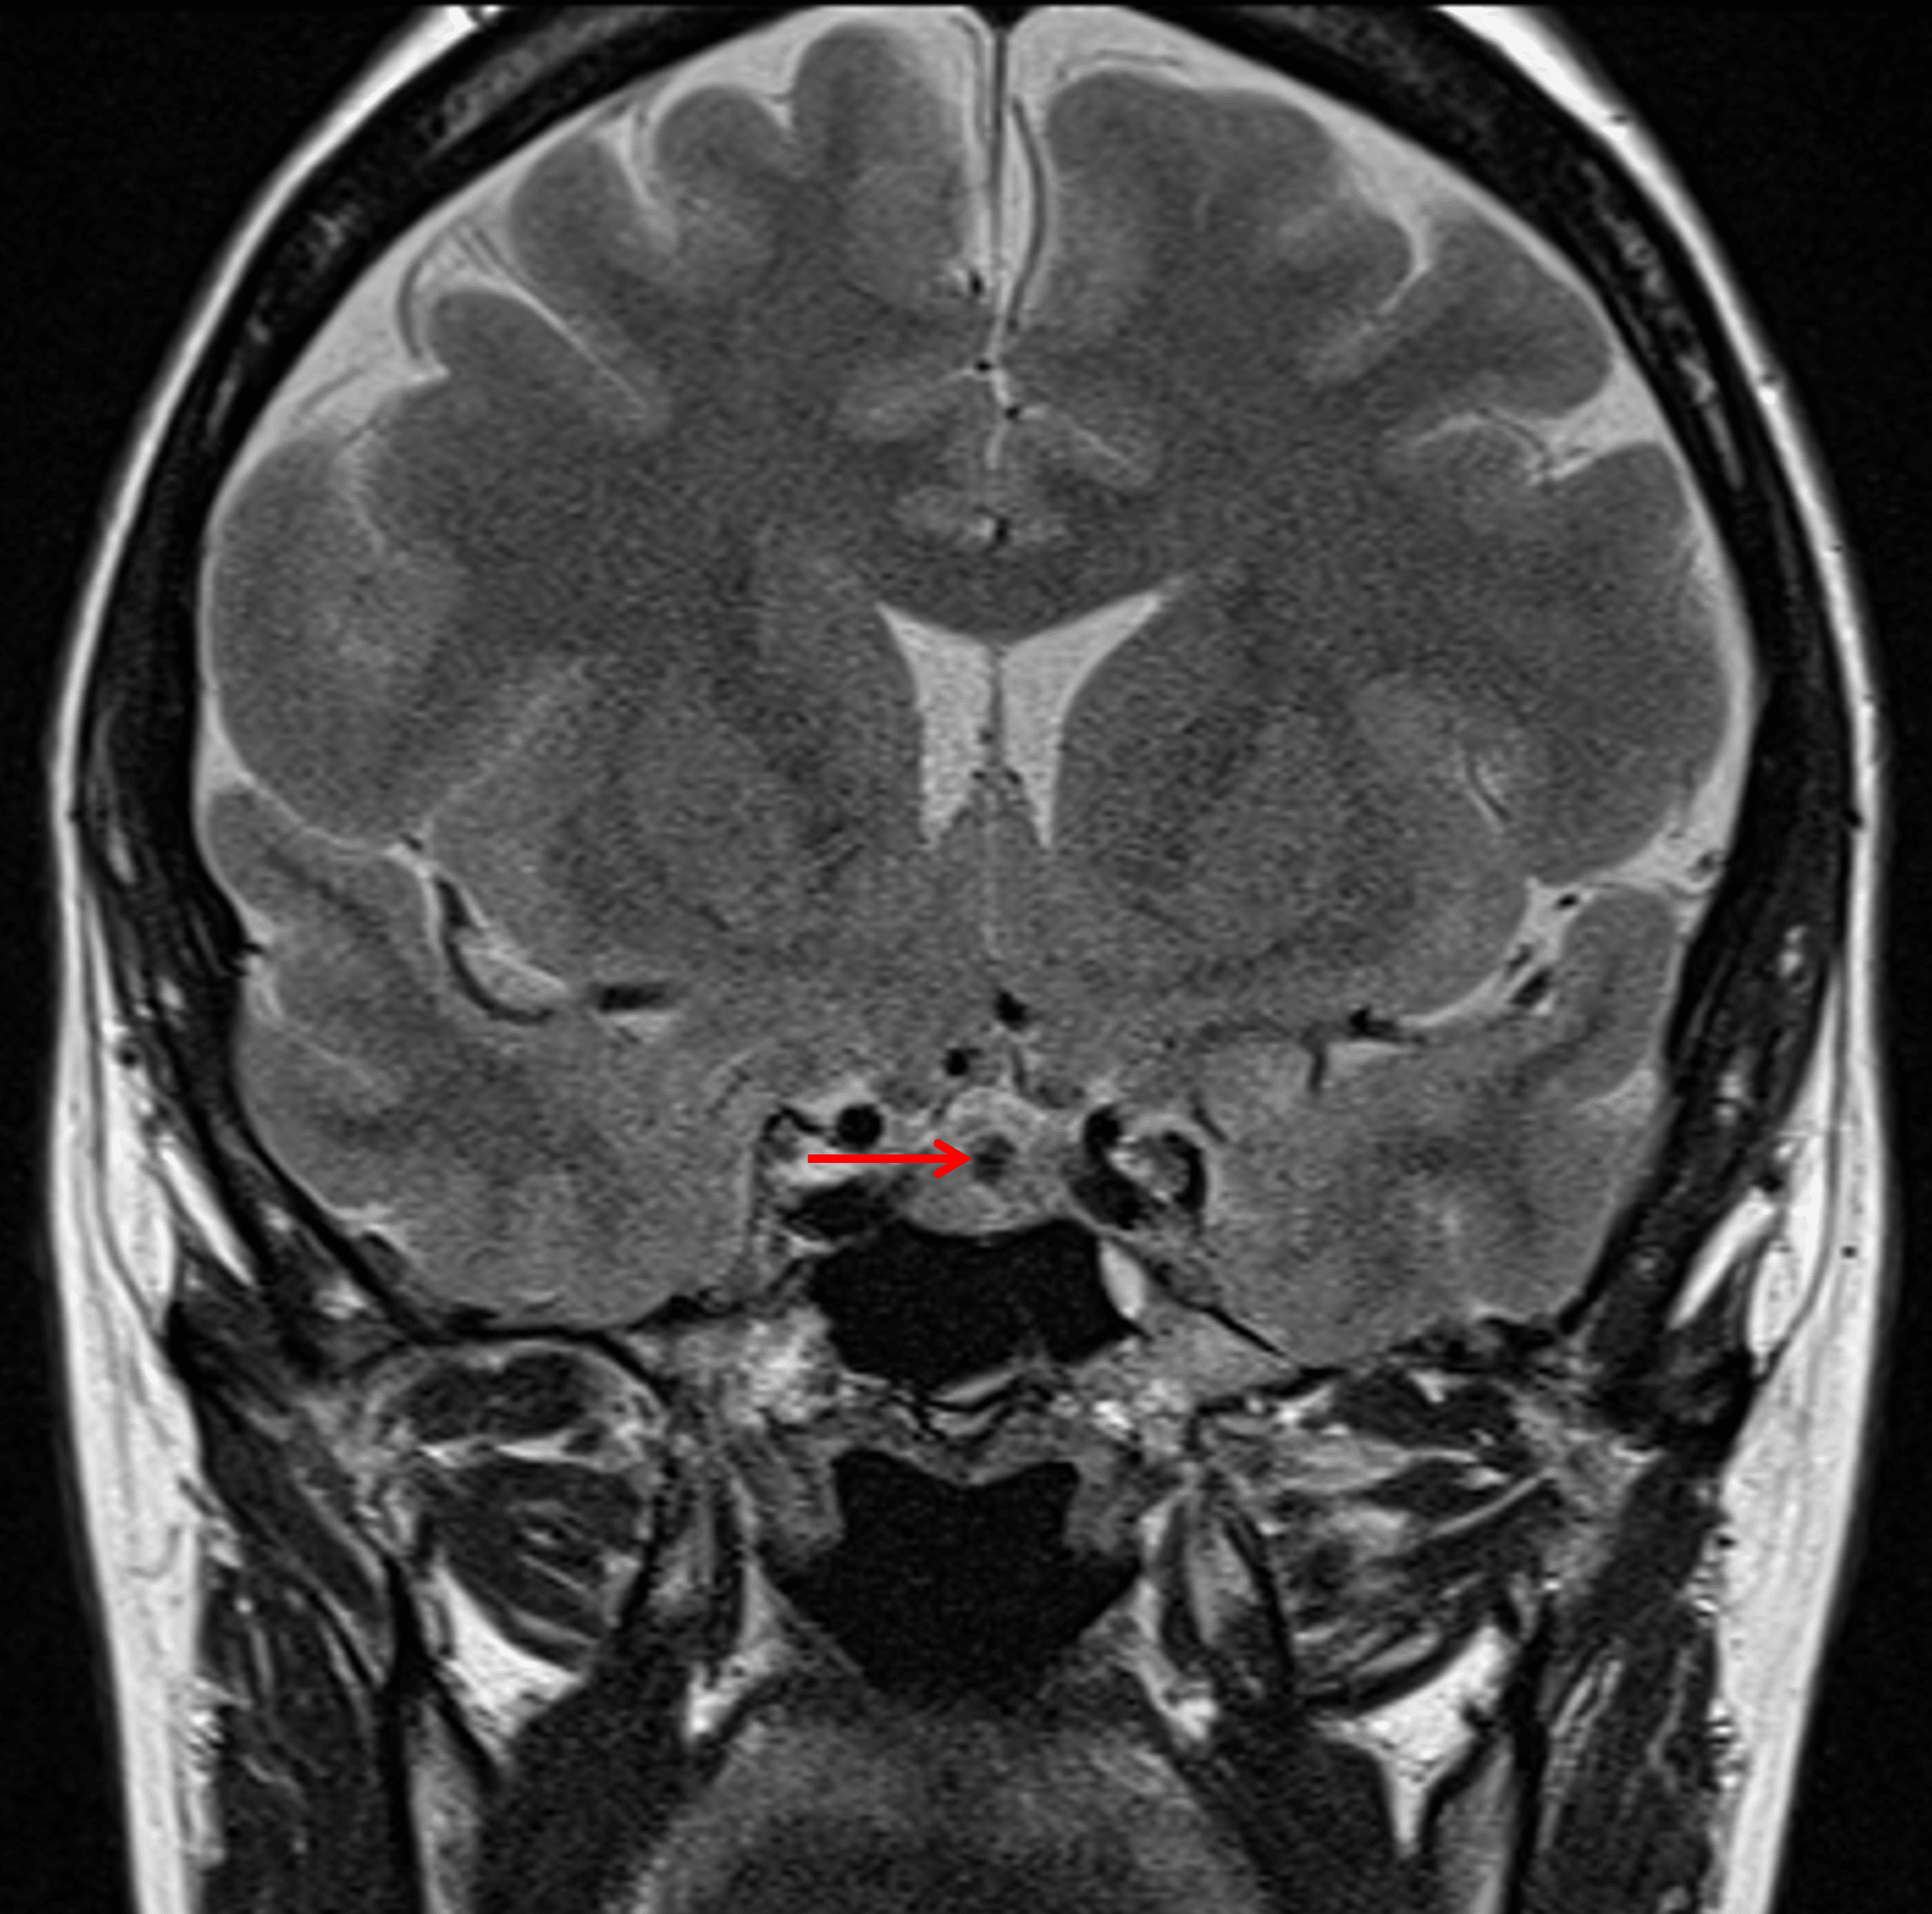

Intralesional T2 hypointense nodule (red arrow), which is a characteristic finding for Rathke cleft cysts.

- Internal rounded area of T2 signal hypointensity measuring 3 mm in diameter

- No corresponding enhancement